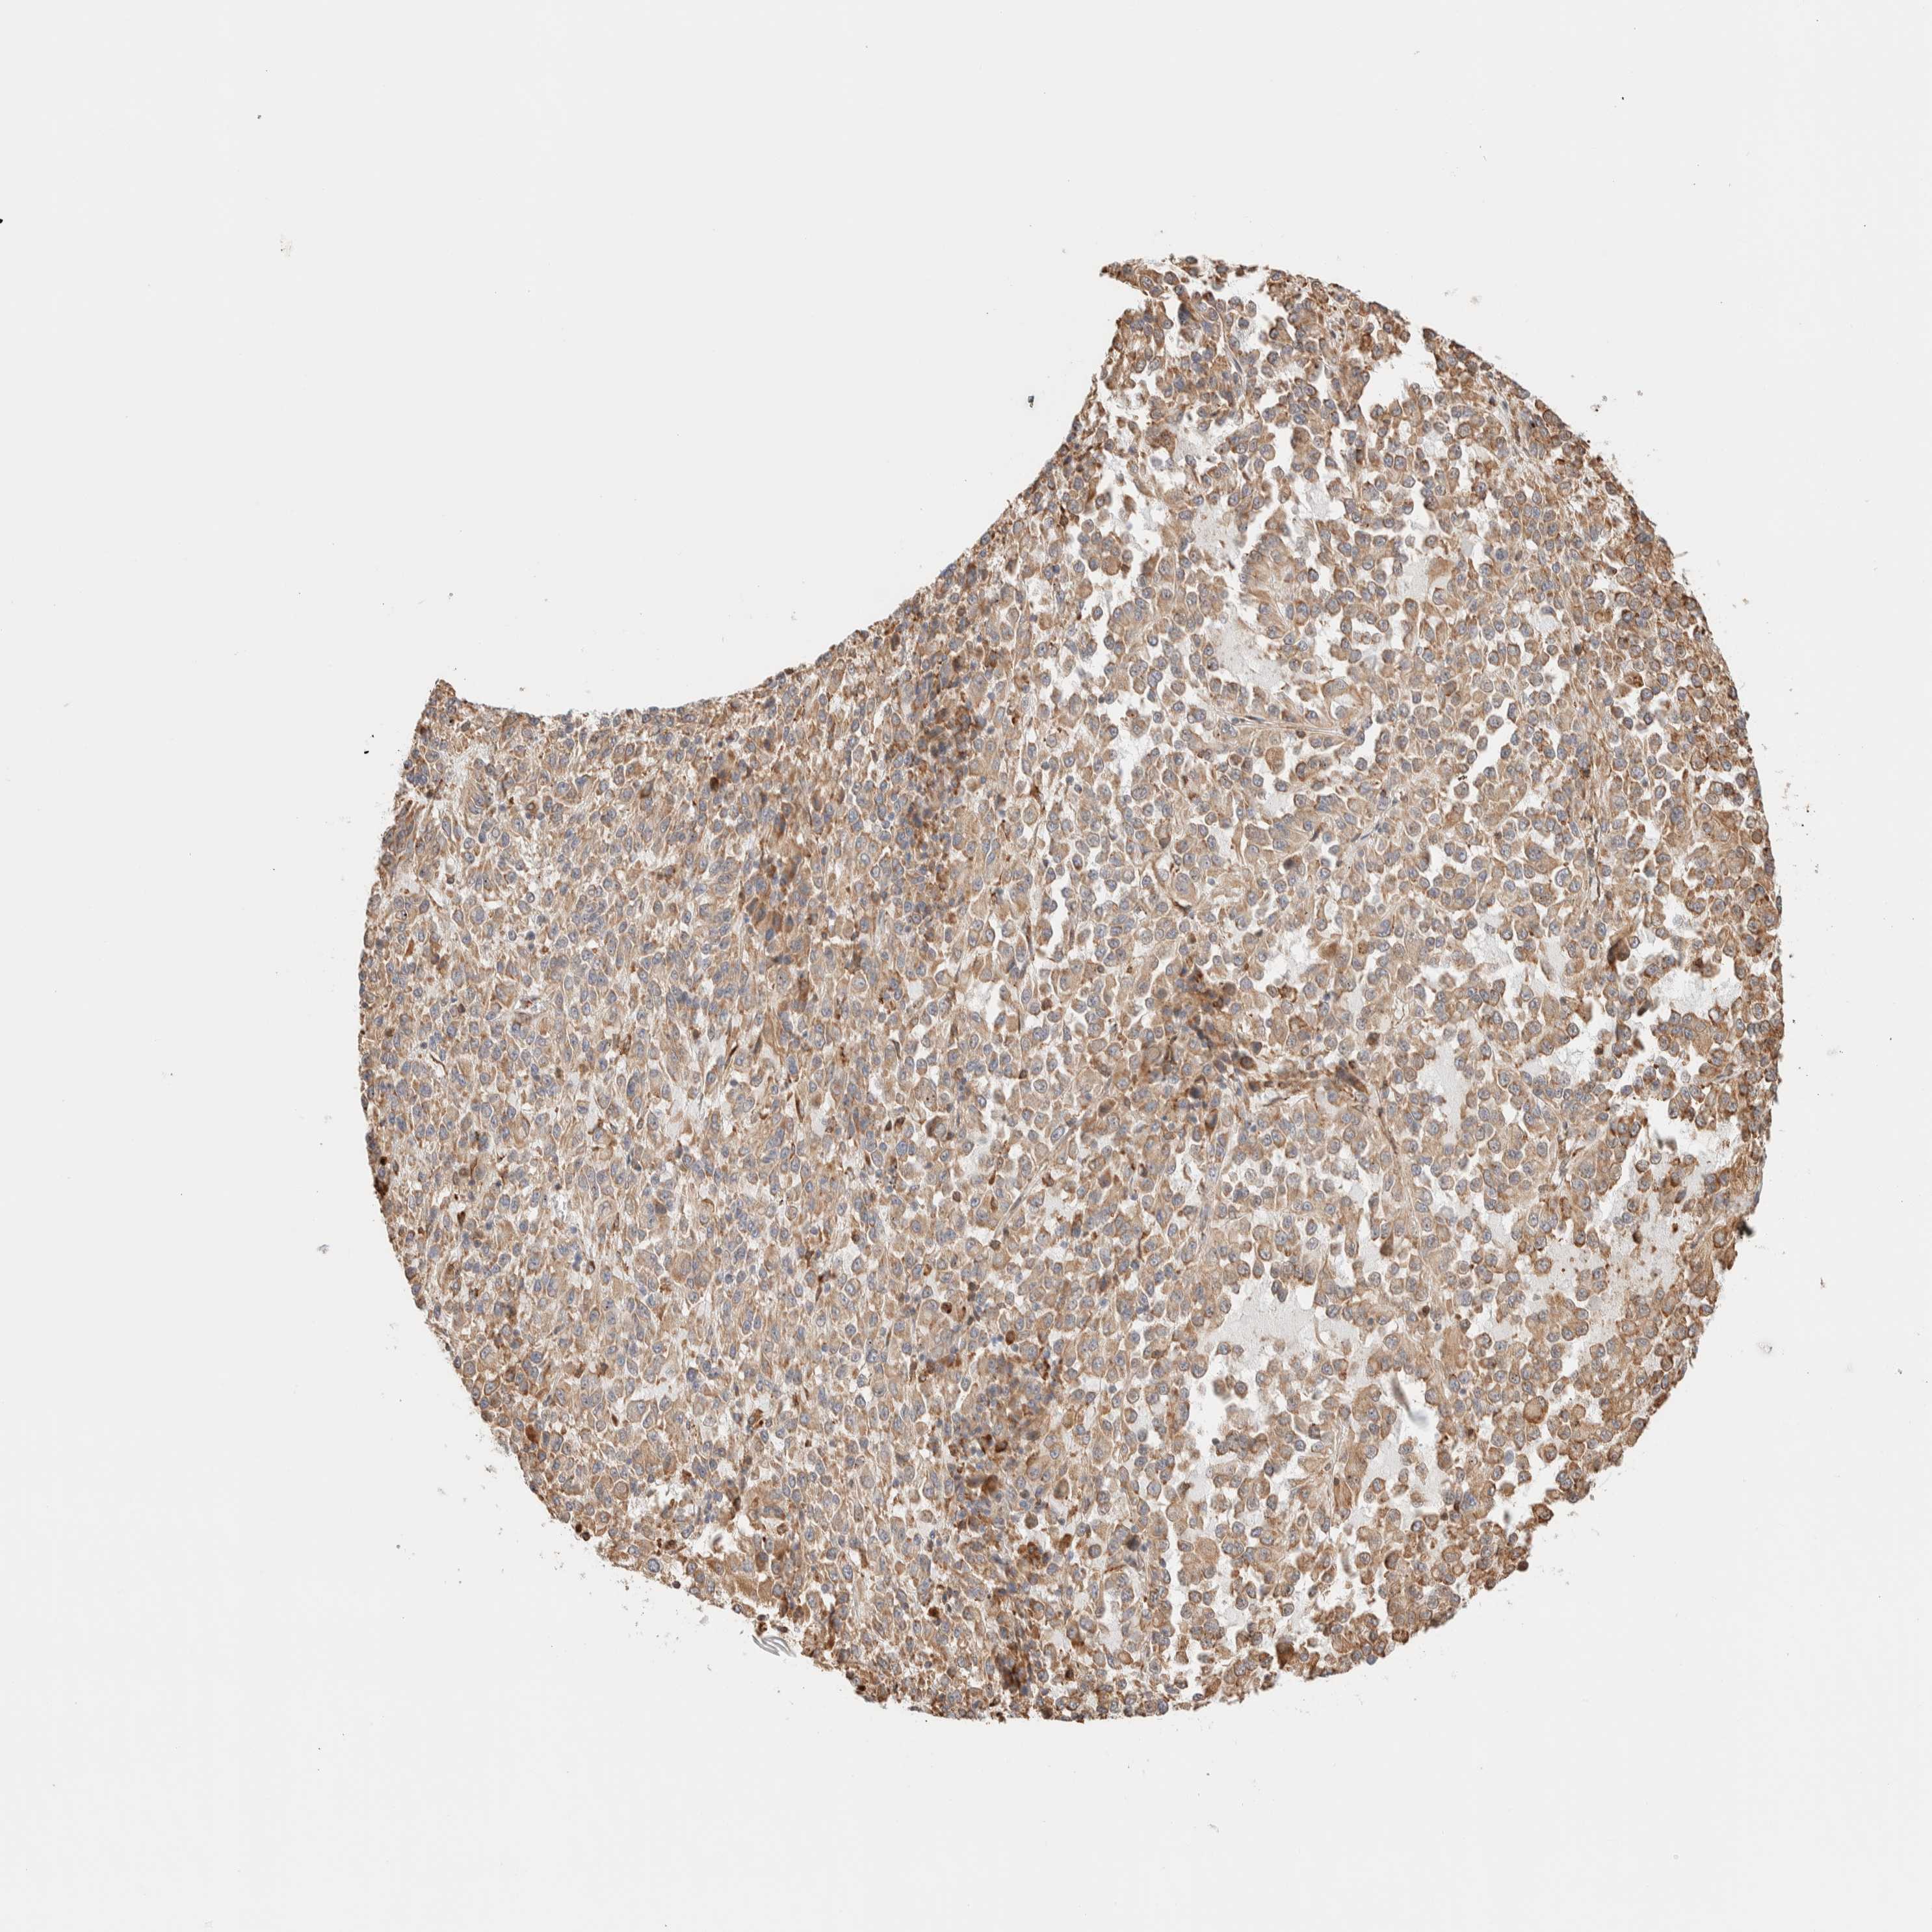

MELANOMA - Protein expressioni

A mouse-over function shows sample information and annotation data. Click on an image to view it in a full screen mode. Samples can be filtered based on level of antibody staining by selecting one or several of the following categories: high, medium, low and not detected. The assay and annotation is described here.

Note that samples used for immunohistochemistry by the Human Protein Atlas do not correspond to samples in the TCGA dataset.

Antibody stainingi

Antibody staining in the annotated cell types in the current human tissue is reported as not detected, low, medium, or high, based on conventional immunohistochemistry profiling in selected tissues. This score is based on the combination of the staining intensity and fraction of stained cells.

Each image is clickable and will lead to virtual microscopy that enables deeper exploration of all samples and also displays staining intensity scores, fraction scores and subcellular localization as well as patient and tissue information for each sample.

Antibody HPA021658

Staining

High

Medium

Low

Not detected

Intensity

Strong

Moderate

Weak

Negative

Quantity

>75%

75%-25%

<25%

None

Location

Nuclear

Cytoplasmic/membranous

Cytoplasmic/membranous,nuclear

Malignant melanoma, NOS

Malignant melanoma, Metastatic site